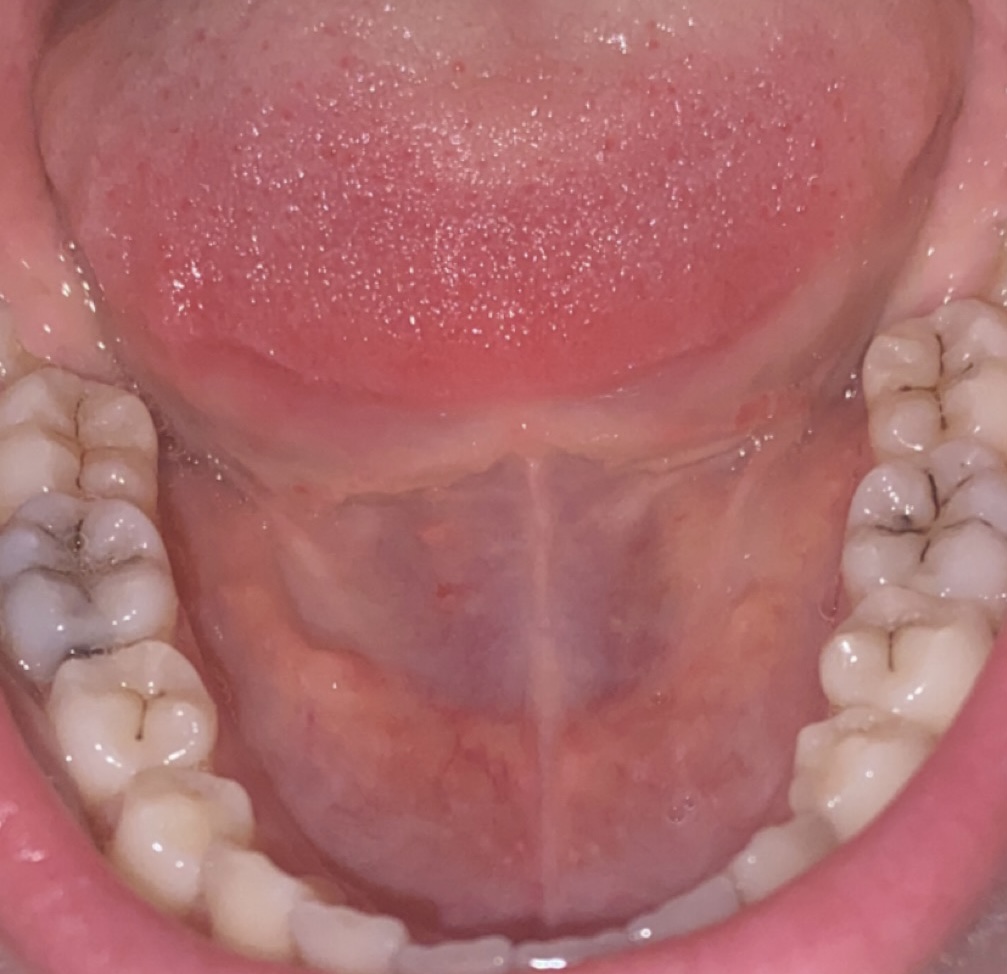

@uzivatel55 ty sa hanbis, a kde mas plomby? ja uz mam kazdu stolicku opecatenu a to sa o zuby staram. nehovorim ze tam nemas kaz. ale cudujem sa ze nevidim plomby. 😂

@uzivatel55 časť ti preplatí poisťovňa, ale tento rok musíš mať preventivku spravenu. A nič hrozné tam nevidím, máš tam všetky zuby🙂 , ver, že sú oveľa horšie prípady

Náhodou máte krásny chrup, ťažko určiť iba podľa foto , ale to čierne by mali byť iba pigmenty, to sa krásne odstráni na dent.hygiene 🙂

Myslím , že tam bude jeden medzizubný kaz..

Z vašej strany v pravo dole medzi 45, 46

Konkrétne 45 distálne 🙂

Možno áno , možno nie to vám už potvrdí dr 🙂

Ale nemáte sa začo hanbiť 🙂

Krásne rovné , bezplombove zúbky 🙂